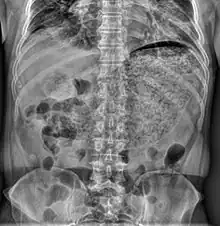

| Simple abdominal X-ray reveals a large amount of material in the stomach, suggesting severe gastric hypomotility | |